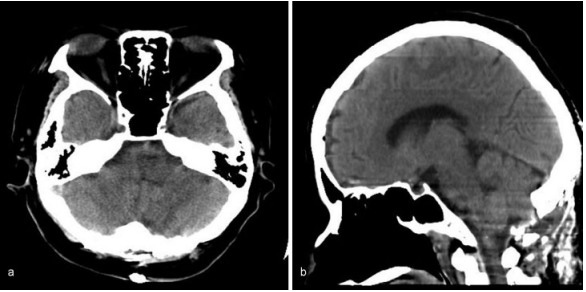

L男士,年龄61岁,头痛、偏瘫、核间性眼震、共济失调走路不稳等,8年前因为发现脑干中脑海绵状血管瘤引起严重脑干出血、生命垂危,当地ICU住院2月保守治疗后好转,并行了脑积水分流手术,发生4次脑干出血,当地医生告知该位置病变手术风险极大、只能保守观察治疗。后得知Helmut Bertalanffy教授在脑干肿瘤手术领域的丰富经验及成功手术病例,便联系“巴教授”进行了会诊,收到教授可以安全全切手术的回复后,奔赴德国住院手术,最终摘除了脑干生命中枢的“炸弹”。

术前MR:脑干中脑巨大占位并发出血